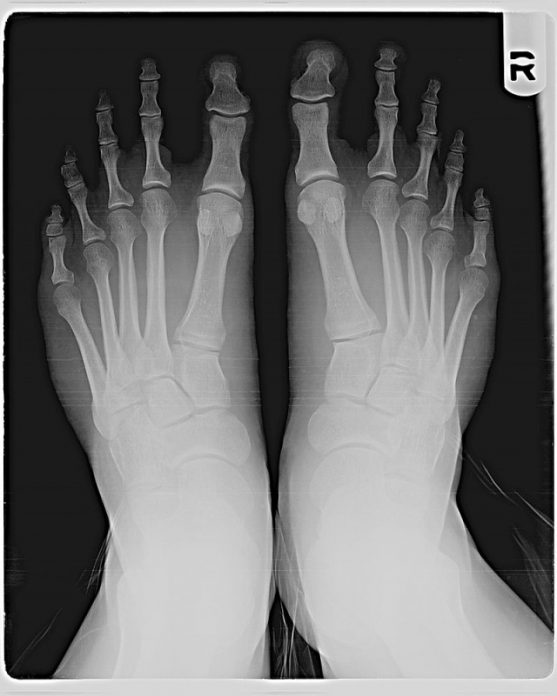

Κάποιοι το ονομάζουν “ελληνικό πόδι.” Είναι σημάδι δύναμης, εξυπνάδας και ελκυστικότητας. Δείτε πώς φαίνεται σε ακτινογραφία:

Οι περισσότεροι πιστεύουν πως η διαφορά είναι μόνο οπτική, αλλά ίσως θα ήταν χρήσιμο να παρατηρούσαμε περισσότερο τα πόδια μας, γιατί αυτό θα μπορούσε να οδηγήσει γρήγορα σε πόνους.

Όταν περπατάτε ή τρέχετε, τα πόδια κουβαλάνε το βάρος μας. Όσοι έχουν το “ελληνικό πόδι” μπορούν εύκολα να αναπτύξουν πόνο στο δεύτερο δάχτυλο, γιατί συχνά λυγίζει. Αυτό μπορεί να προκαλέσει φλεγμονή στην άρθρωση και μερικές φορές είναι πολύ επίπονο. Ο κίνδυνος είναι αυξημένος για δρομείς.